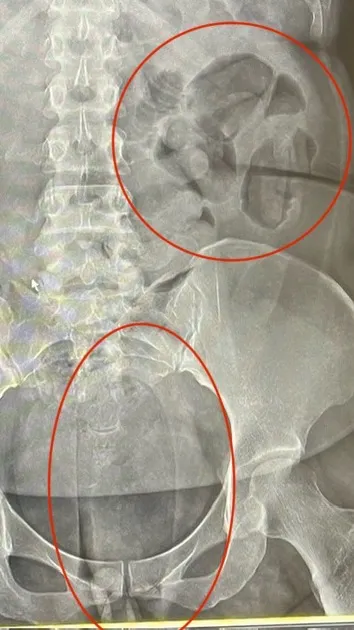

X光片顯示運毒手體內有大量毒膠囊。翻攝照片